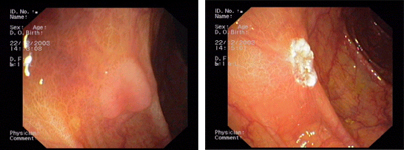

imagen2

Kaposi's sarcoma in the stomach - Submucosal tumour of the oesophagus